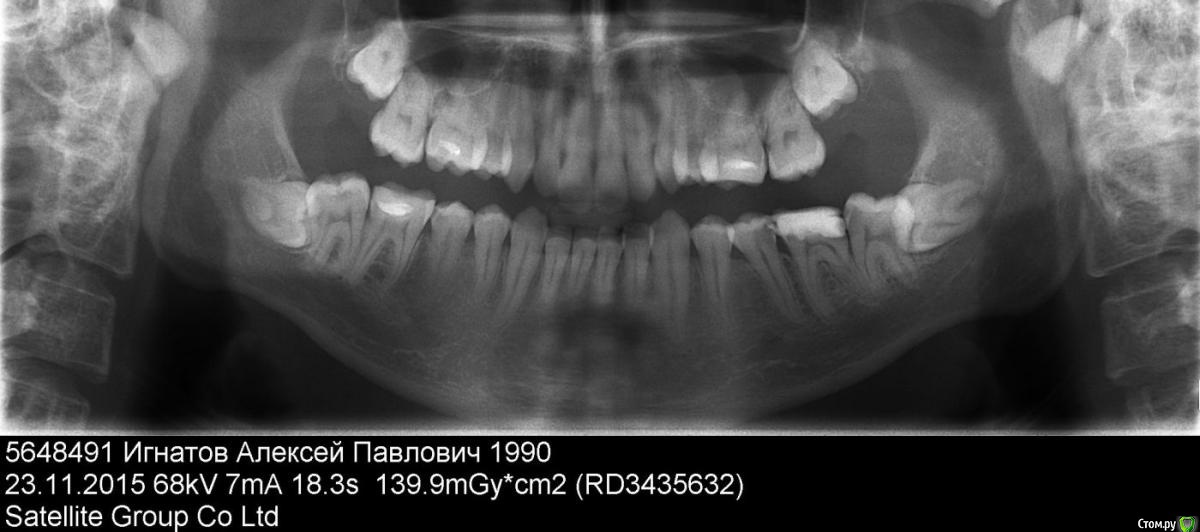

LexIgnatov Опубликовано 1 декабря, 2015 Автор Поделиться Опубликовано 1 декабря, 2015 (изменено) Здравствуйте. Вновь прошу совета.Итак, в "предыдущих сериях"... Шестой зуб слева для меня (Или справа глазами доктора).Исходное состояние перед лечением:Не очень понимаю что где, но для лечения обратился потому что отвалилась пломба на этом зубе.17.11.2015 Убран глубокий кариес, положена какая-то мазь для заживления-успокоения нерва. Через день нерв начал стрелять.20.11.2015 Положили параформальдегидную (насколько я понял) пасту для умерщвления нерва (позже выяснилось что там 4 канала). Боли сменились на лёгкие ноющие с редкими покалываниями.23.11.2015 Сделан снимок ОПТГ.Записали на приём 5.12.2015 к стоматологу-ортодонту, чтобы решить что делать с 7 и 8 зубами. Дело в том, что 7-й зуб наполовину сверху прикрыт десной. А на открытой части виден кариес. Сказали что если ортодонт скажет, что можно сохранить 7 и 8 зубы, то нужно удалить часть десны над 7-ым и попробовать вылечить кариес. Говорят что судя по снимку нервы в нём можно будет не удалять. Пугает, что когда 6-й лечили, тоже говорили, что попытаются сохранить нервы - однако после болей пришлось их удалить. Проблема в том, что у меня рот плохо открывается, и если потребуется депульпирование 7-го, то туда будет очень сложно залезть. Другой вариант как они сказали - удалить 7-ки, а через их полость удалить и 8-ки. Но это меня пугает, всю челюсть перепахают. У матери (50 лет) 8-ки до сих пор не прорезались и не беспокоят.27.11.2015 Удалили 4 нерва в 6-м зубе без анастезии. Два нерва удалялись с болью несмотря на девитализацию, сделали внутрь каналов местную анестезию - пошло лучше. Во время чистки каналов где-то сильно дёргало, чистили пока не перестало дёргать. Поставили гуттаперчи с противовоспалительным раствором и временную пломбу на 11 дней. Сказали что потом будут ещё раз чистить каналы и пломбировать их на постоянку. Зачем второй раз чистить? Не хочу снова подпрыгивать в кресле))Снимок в процессе установки гуттаперчи:PS. Ещё не понятно как восстановить коронковую часть зуба. От него фактически остались две стенки - со стороны щеки и языка, а остальное пломба. Хочется понять как грамотнее поступить, что посоветуете? Спасибо.PS2. Редкие слегка покалывающие боли сейчас (пока лежит противовоспалительное) в моём случае нормально или нет? Иногда ощущение, что от пульса отдаёт, при приседании. А иногда даже от активной мимики. Или это может реагировать плохой соседний пятый зуб? И можно ли есть на таком зубе? Я вот побаиваюсь и ем на другой стороне. Изменено 1 декабря, 2015 пользователем LexIgnatov Ссылка на комментарий